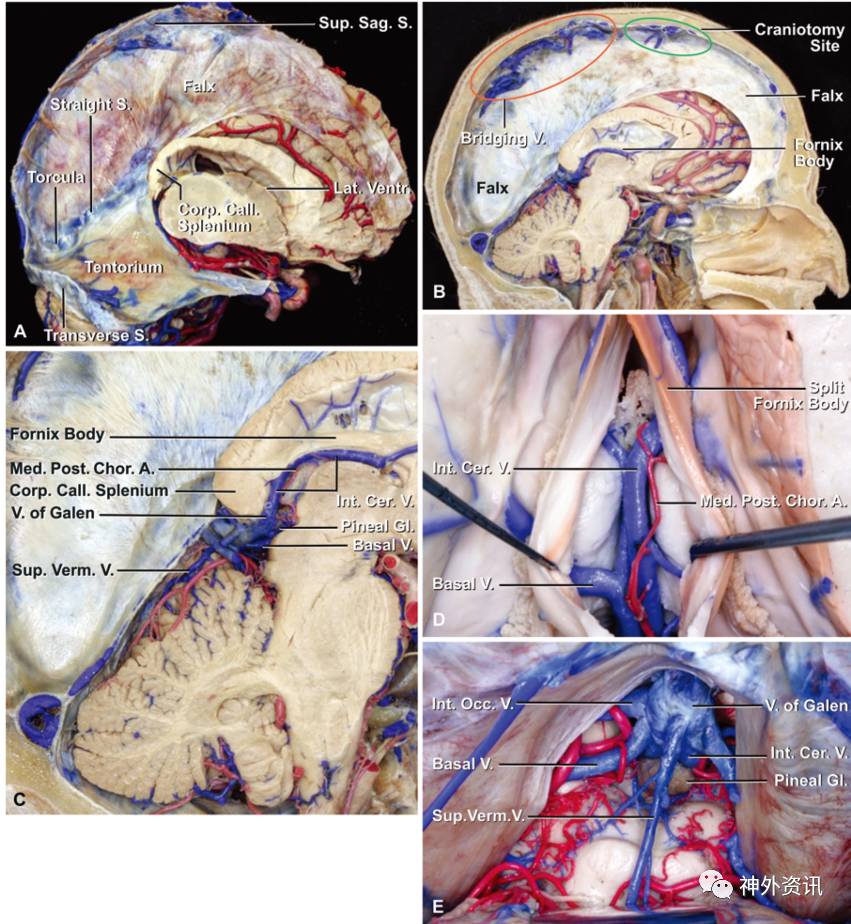

图1. 松果体区结构的解剖关系。A.切除右侧大脑半球后,显露大脑镰和小脑幕。大脑镰后部下缘呈斜行向胼胝体压部,于中线处与小脑幕交汇。直窦起源于胼胝体压部下方。B.内侧面观:冠状缝下方的脑表面几乎没有桥静脉,然而在顶叶存在许多桥静脉。C.内侧面观:松果体位于Galen静脉下方。大脑内静脉穿过中间髓帆,与Rosenthal基底静脉在胼胝体压部下方汇合成Galen静脉。D.上面观:切开穹窿体和穹隆连合(海马连合)暴露深部的静脉结构以及中间帆内的脉络膜后内侧动脉。E.后面观:松果体及其与深部静脉结构的关系。